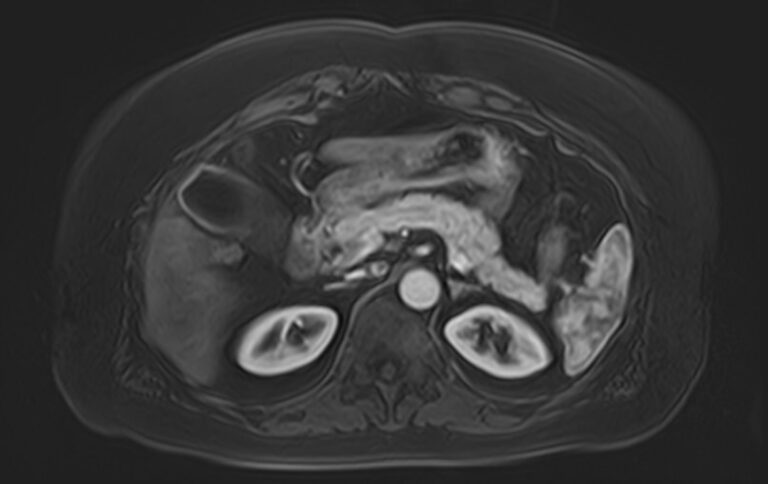

Магнитно-резонансная томография является высокоинформативным методом диагностики почечной патологии. Метод основан на применении внешнего магнитного поля без использования рентгеновского излучения, что делает процедуру безопасной для организма человека.

МРТ почек проводится для оценки состояния всех структур почек, включая паренхиму, чашечки, лоханки почек и верхние отделы мочеточников. В клинике «Доступная медицина» исследование выполняется на томографе экспертного уровня TOSHIBA VANTAGE TITAN 1,5 Тесла, который обеспечивает изображения высокой четкости и контрастности, что позволяет проводить точную и достоверную диагностику заболеваний почек.